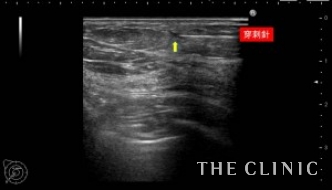

この方は、10年前に脂肪注入を受けられていて、近年の乳がん検診にてしこりを指摘されたとのこと。指摘後は何もせず放置していたが、昨年ぐらいから自分でもしこりを感じるようになったため、当院を受診されました。

しこりの大きさは3mmから7mmと非常に小さなしこりでしたが、ご本人が治療を希望されたためエコー下に穿刺吸引しました。右のしこりの1つは乳腺内の腫瘤でしたが濃縮のう胞でした。

吸引した脂肪です。両側合わせて12個のオイルシストを穿刺吸引しました。